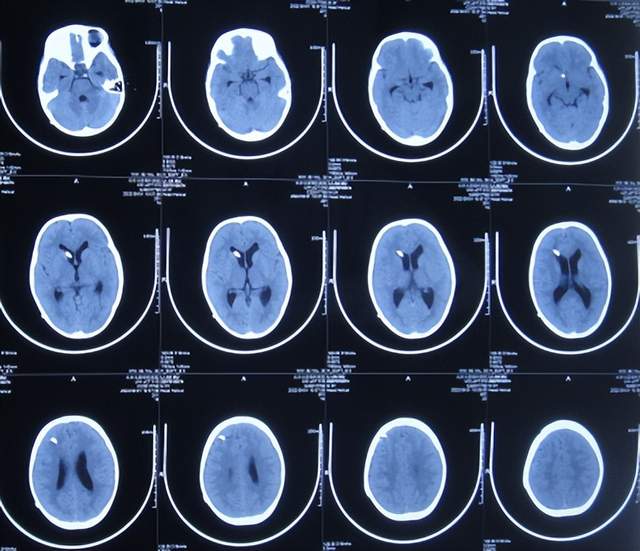

住院治疗7天即2022年5月18日,出现头痛,呕吐,体温再次升高为39.6度,心电图示室性心动过速,室早,考虑“心肌炎”,查头颅核磁(图-1)后并行腰穿见脑脊液呈金黄色,留取脑脊液送常规化验提示诊断为颅内感染,给予抗感染治疗。

图-1:2022年5月18日头颅核磁

第3家医院治疗16天即2022年6月9日,不但依然发热,而且查头颅CT示脑室稍扩张(图-3)。

图-3:2022年6月9日头颅核磁

但该院治疗12天即2022年6月29日,复查头颅核磁脑室扩张进一步加重(图-6)。

图-6:2022年6月29日头颅核磁

入院当天查头颅CT示脑室扩张(图-8)。

图-8:2022年7月1日入院时头颅CT

住院治疗18天即2022年7月18日,查头颅CT示脑室有缩小(图-12)。

图-12:2022年7月18日头颅CT

住院治疗63天即2022年9月1日,常规查头颅CT示脑室引流术后状态(图-15)。

图-15:2022年9月1日头颅CT

2022年10月12日(住院治疗104天),已夹闭脑室引流管3天,查头颅CT示脑室未见异常(图-17)。

图-17:2022年10月12日头颅CT

2022年10月25日(李小勇脑脊液科治疗117天),出院时:精神状态挺好,大小便正常,虽右腿走路稍差但走路速度变快,变稳(图-19);出院时头颅CT示未见异常(图-20)。

图-20:出院时头颅CT